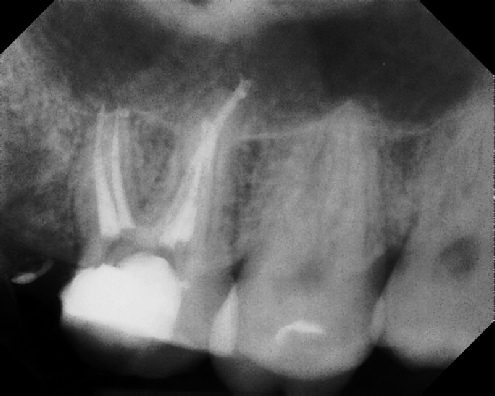

Root Canal Retreatment - Meriden 8 mos. recall Post-op Pre-op